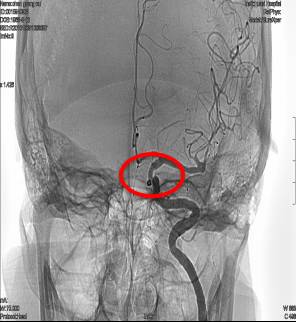

术后造影动脉瘤均未显影,载瘤动脉通畅。

三月后复查动脉瘤未复发,载瘤动脉通畅。